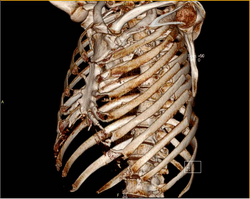

Sumnja na prijelom rebara najpouzdanije se potvrđuje;

- radiografijom prsnoga koša u nekoliko pravaca,

- ultrazvučnim pregledom

- kompjuteriziranom tomografijom.

Dijagnostika prijeloma rebra nije uvijek laka, kao i dijagnostika komplikacija ovih prijeloma koji moraju pravodobno biti uočeni jer mogu životno ugroziti povrijeđenog zbog; krvarenja, ozljeda srčane i plućne maramice, pluća i organa trbuha.

Također radiološkim dijagnostikom treba isključiti i moguće druge ozljede koje mogu biti udružene sa prijelomom rebara.